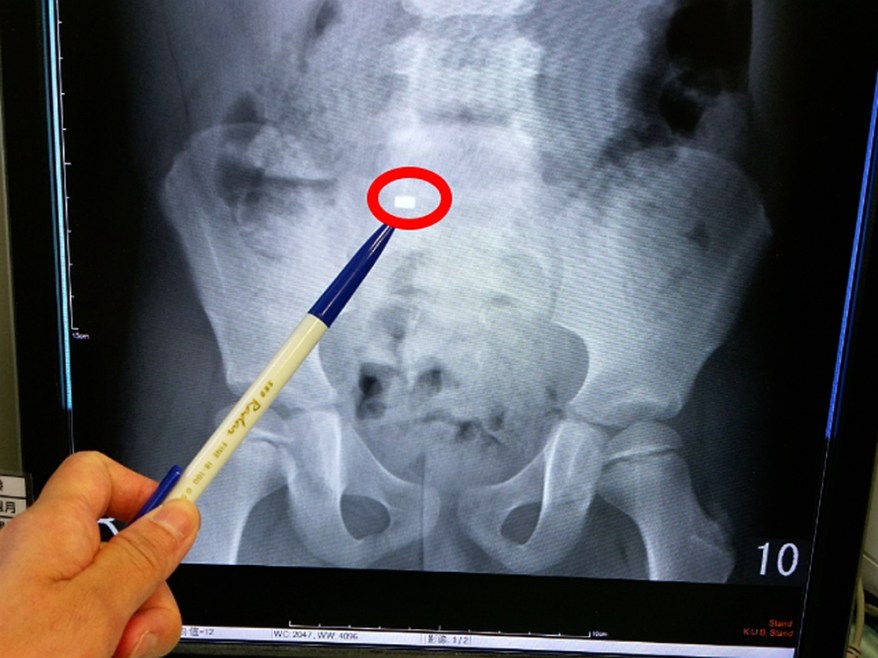

[新媒社 記者張銀澤/台中報導] 五歲王姓女童日前玩耍時,不小心吞進一顆0.5公分磁鐵,媽媽來不及阻止,雖沒有明顯腹部不舒服,但家人還是趕緊帶她至長安醫院急診就醫。經急診醫師仔細做腹部理學檢查及腹部X光,發現那枚磁鐵已落到女童小腸部分,且腹部X光無腸胃道穿孔情形。會診兒科韓舒萍醫師,再三和家人確認只吞食一枚磁鐵後,觀察無發燒及其他腹部不適的症狀,如腹痛、腹脹、嘔吐、血便、黑便,女童後續也順利經由排便將磁鐵排出,虛驚一場。